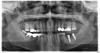

Uma Опубликовано 13 апреля, 2013 Автор Поделиться Опубликовано 13 апреля, 2013 (изменено) Ничего не скажем без снимка Есть снимок сделан через 3 месяца после имплантации в другой клинике. В ходе моих ортопедических приключений никто снимок не делал. Изменено 13 апреля, 2013 пользователем Uma Ссылка на комментарий

Uma Опубликовано 13 апреля, 2013 Автор Поделиться Опубликовано 13 апреля, 2013 нужно проверить по-другому.Для начала нужно сделать новый снимокСнимок, который я разместила сделан полтора месяца назад. Через 3 месяца после имплантации. Еще надо делать? Глядя на этот снимок мне сказали, что приживление прошло нормально, можно протезироваться. Боли в кости при жевании не возникало. Болела десна и зуб (больше всего верхняя семерка) в который упиралась нижняя коронка. Ссылка на комментарий

IvanK Опубликовано 14 апреля, 2013 Поделиться Опубликовано 14 апреля, 2013 Советую обратить внимания на другие зубы http://s020.radikal.ru/i722/1304/eb/745cf7ec3b4f.jpg Ссылка на комментарий